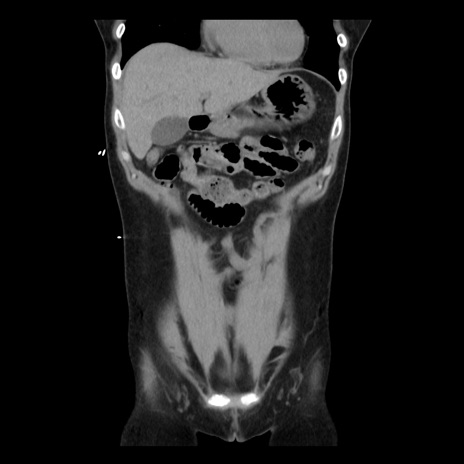

症例10(冠状断像)

【症例】 50歳代女性

【主訴】 腹痛

【現病歴】前日生レバーを食べた。今朝に排便あり。 昼前に突然発症の腹痛を生じ、当院救急外来を受診した。

【既往歴】 子宮筋腫にてで子宮全摘後

【身体所見】 意識清明、腹部:平坦、軟、下腹部やや左を中心に圧痛・反跳痛あり、筋性防御あり

【データ】WBC 7800、CRP 0.07